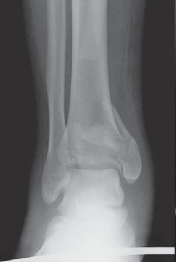

5.

The diagnosis of tibial plafond fracture is initially evaluated with three radiographic views of the ankle (anteroposterior [AP], mortise, and lateral; FIG 4A,B).

CT scans have been clearly shown to improve a surgeon’s understanding of the injury ( FIG 4C) and are critical to preoperative planning for complex injuries.15

7.

For displaced, comminuted pilon fractures, the best time to obtain a CT scan is after temporizing external fixation is performed ( FIG 4D), when the fracture is brought out to length with traction. This tends to grossly reduce many parts of the fracture, making the pathoanatomy of the injury more understandable (FIG 4E,F).